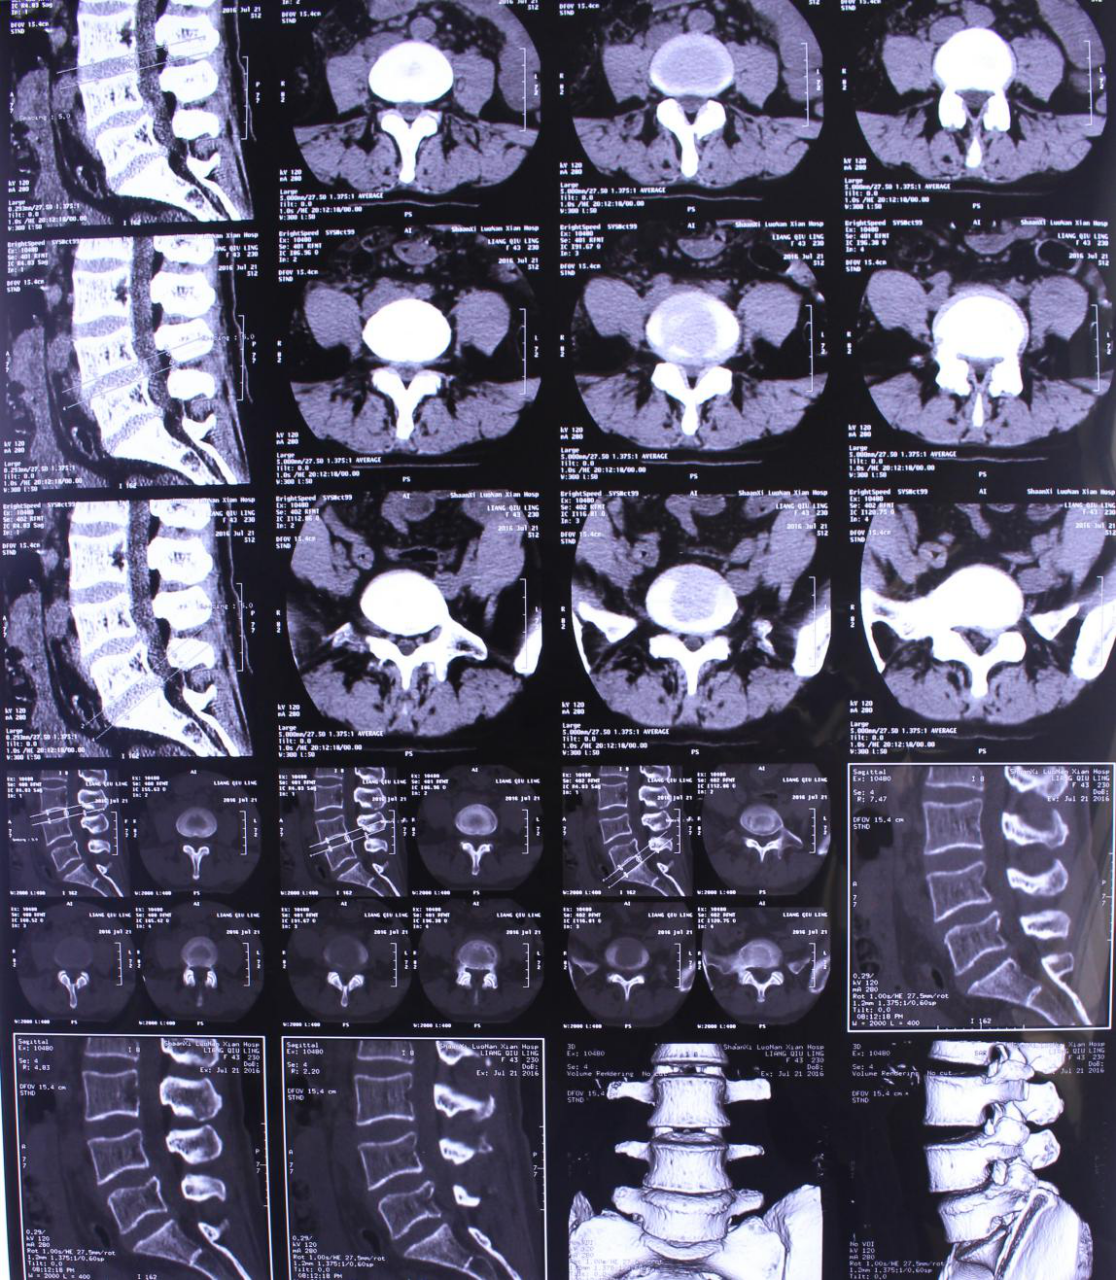

椎间孔镜技术治疗腰椎间盘突出症一例